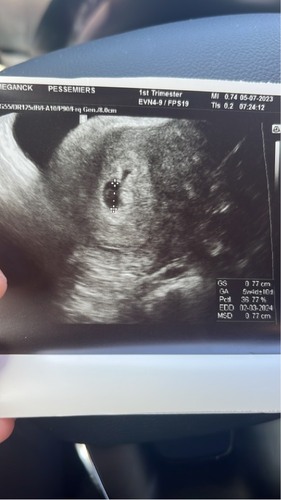

Ik ben 6w en heb gisteren een giga enorme bloeding gehad met krampen en stolsels. Het ergste scenario ging door m’n hoofd en ik ben gelijk in mn auto gesprongen en naar het ziekenhuis gereden. Uiteindelijk bleek dat er een adertje gesproken is en dit een hematoom veroorzaakte. Met het kleintje was alles goed. Het hoeft dus zeker niks super erg te zijn!